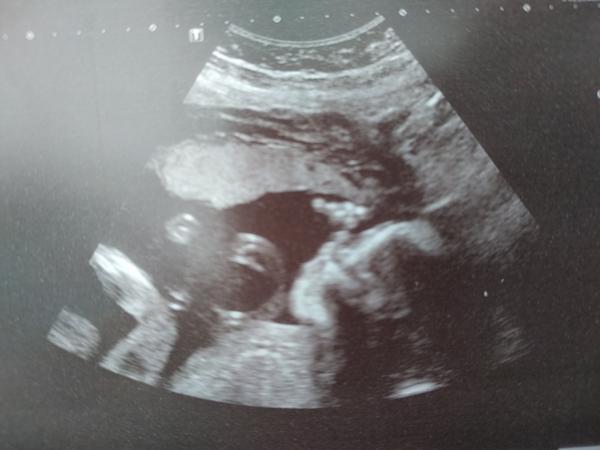

Mimochodem takys na tom UTZ dostala jen tak fotku? Koukala jsem na něj jako blázen když mi ji podával 😀

@vilmic já už právě fotku nechtěla ani na tom druhém screeningu, protože jsem říkala, že za tu stovku co za ní chtějí koupím pro prcka radši něco na sebe 😀 ale dneska se mě neptal jestli ji chci, prostě mi ji vrazil do ruky se zprávou. Ale ono na ni stejně není nic vidět 😀 ja jestli jsem to dobře pochopila, tak budu mít další UTZ teda asi taky za měsíc. Tak se tam třeba zase potkáme 😀